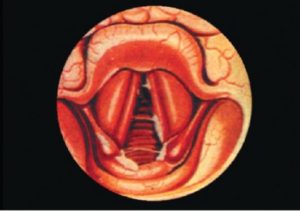

При осмотре гортани определяются признаки катарального воспаления в подскладочном пространстве: покраснение и отек слизистой оболочки. Определяется симметричная припухлость в виде валиков, которая выходит за пределы ых связок, мешая прохождению воздуха. Не исключен и геморрагический ларингит, например, на фоне гриппа – тогда будут видны кровоизлияния.

- Длительный вдох и короткий шумный выдох.

Изменения в гортани (сужение дыхательных путей) при подскладочном ларингите